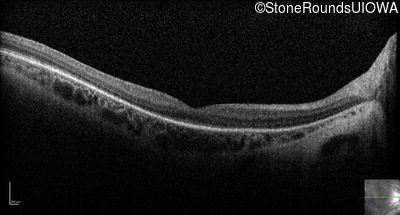

Age at visit: 14 years